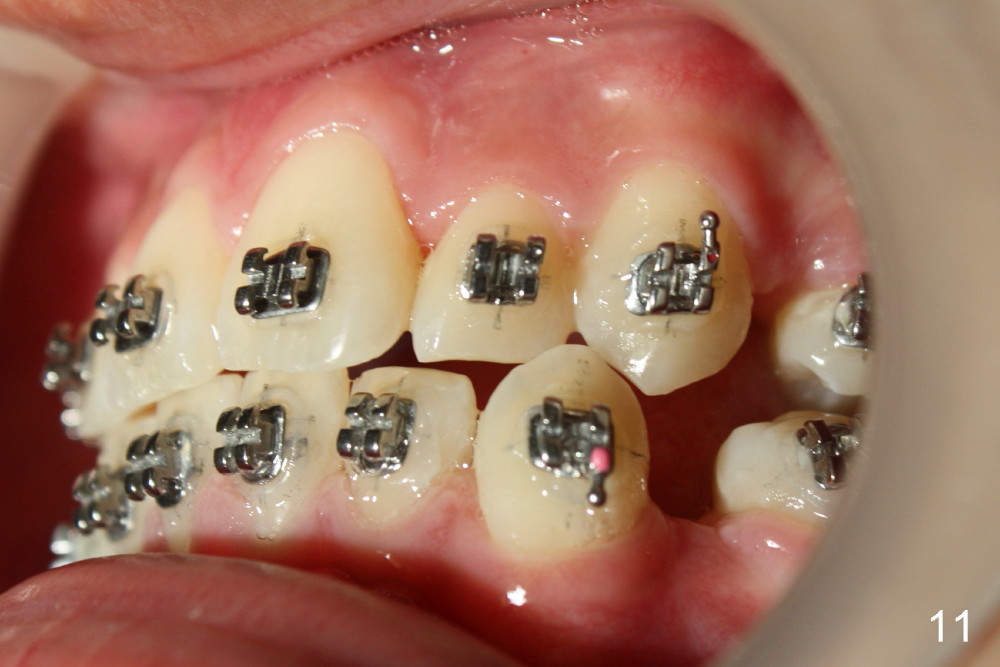

A 13-year-old boy has severe crowding (Fig.1-5). Four of the first bicuspids were extracted on 02/17/2014. Full mouth brackets or bands (except #18) were placed on 03/27/2014. Alignment improved 2 months later (Fig.11, 05/24/2014). The upper 18 ss wire was modified (Fig.12), and fixed with alastiks (Fig.13,14). One month later (07/01/2014), local alignment also improved (Fig.15); the upper modification is confined to one tooth.